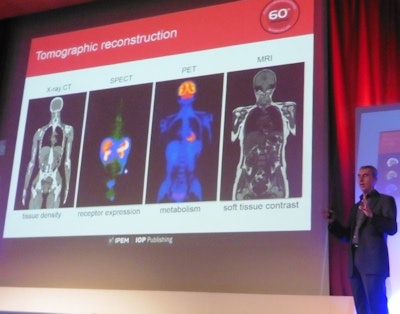

Meikle examined the major advances that enabled this "medical physics revolution." "In imaging, I nominate tomographic reconstruction as the single biggest advance that moved the field forward," he declared. Indeed, the significance of this development was recognized back in 1979, when Allan Cormack and Godfrey Hounsfield won the Nobel Prize in Physiology or Medicine for their development of computer-assisted tomography.

In radiotherapy, major advances concern the emergence of conformal radiotherapy, including beam shaping with multileaf collimators in the 1980s, IMRT in the 1990s, and IGRT in the 2000s. "All of these progress radiotherapy treatment planning and delivery to allow much more conformal and precise dose distributions," he said.